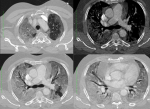

Case 2: is a known diabetic with poor glycaemic control admitted via the emergency room on account of cough and difficulty in breathing of 5 days duration as well as diarrhoea. He was afebrile and had reduced air entry in both lungs. He had hypoxaemia improving on oxygen therapy and on lying prone. His radiograph showed bilateral, nodular opacities with a peripheral and predominantly lower lung zone distribution (Figure 2). His full blood count was normal, d-dimer and CRP were elevated, liver function tests deranged. His COVID-19 RT-PCR test results were positive and he was evacuated to the isolation centre for further management.

Cases 2 and 4, with difficulty in breathing had oxygen saturations of 90% or less despite oxygen supplementation and this improved moderately on nursing prone. In index case 3, the clinical condition worsened and progressed to death despite mechanical ventilation. Hypoxaemia is reported to provide a robust risk factor for fatal outcomes and is associated with death in patients with COVID-19-associated pneumonia independently of age and sex [7]. It is also associated with higher neutrophil counts, D-dimer and CRP levels as well as acute inflammation of the respiratory system, caused by respiratory virus or secondary bacterial infection [7]. CRP and D-dimer were elevated in the more severe 3 of our index cases, also consistent with a moderate to severe inflammatory process [8]. Imaging for COVID-19 pneumonia mainly comprises chest radiography and computed tomography (CT). Our patients underwent X-rays and computed tomography scans. Chest radiographs are an initial and quick method of evaluating for significant lung abnormality. They may be less sensitive than CT, but are widely available, cost-effective and are suitable for primary hospitals which do not have CT machines as well as for the bedside examination of critically ill patients. Where there is high clinical suspicion of COVID-19, it is possible that a positive CXR may obviate the need for a CT [9]. Up to 89% of X-rays in COVID-19 may be interpreted as normal or mildly abnormal [10]. This is similar to findings in our patients as the x-ray in case 1 was normal while the chest X-ray in case 2 showed ill-defined bilateral alveolar consolidation with a peripheral and lower lobe distribution. It also excluded other pathology such as pneumothorax or pleural effusion. The other two cases did not have chest X-rays.

CT is the gold-standard for detecting the presence of lesions in the lungs, especially high-resolution CT, as it has no overlapping structural interference and can detect small lesions. It is useful for the diagnosis and differential diagnosis of COVID-19, monitoring treatment outcomes and early detection of other complications [3]. In the early stage, it shows multiple small patchy ground glass and interstitial changes, then develops into multiple ground glass shadows and infiltration with a peripheral distribution [3, 8], similar to the changes seen in our index cases 2 and 4. Ground-glass opacification is a slightly higher density, usually-rounded and blurred lesion in the lungs, where the pulmonary blood vessels are visible [1]. The ground-glass and/or consolidative opacities are usually bilateral, peripheral, and basal in distribution [1, 11]. This may be explained by viral invasion and replication in the bronchioles and alveolar epithelium causing inflammation and thickening of the alveolar wall with a distribution mainly around the lung and under the pleura [3]. In more severe cases, pulmonary consolidation may occur. Consolidation may be related to acute diffuse alveolar injury, including oedema, red blood cells and cellulose deposition. Thickening of the pulmonary interstitium or fibrosis may also be seen as stripes [3]. Pleural effusion and pneumothorax are rare [4]. Our cases run the gamut from mild to moderate to severe. Case 1 was a mild type with mild clinical symptoms and imaging findings showed no features of pneumonia. The chest CT manifestations of COVID-19 often presented patchy ground-glass opacities or mixed ground-glass opacities and consolidation, predominantly involving the periphery of both lungs, that can change rapidly [8]. Li et al. in a multicentre study in China showed that some patients with normal chest CT imaging could test positive for COVID-19 [8]. Cases 2 and 4 were of moderate severity with fever, cough, hypoxia and bilateral peripheral infiltrates, predominantly in the lower lobe in case 2. These findings are consistent with the findings described in other studies as the disease progresses [3, 8].

Figure 2: chest radiograph of case 2 on the 5th day of onset of symptoms, showing bilateral nodular opacities with a peripheral and predominantly lower lung zone distribution